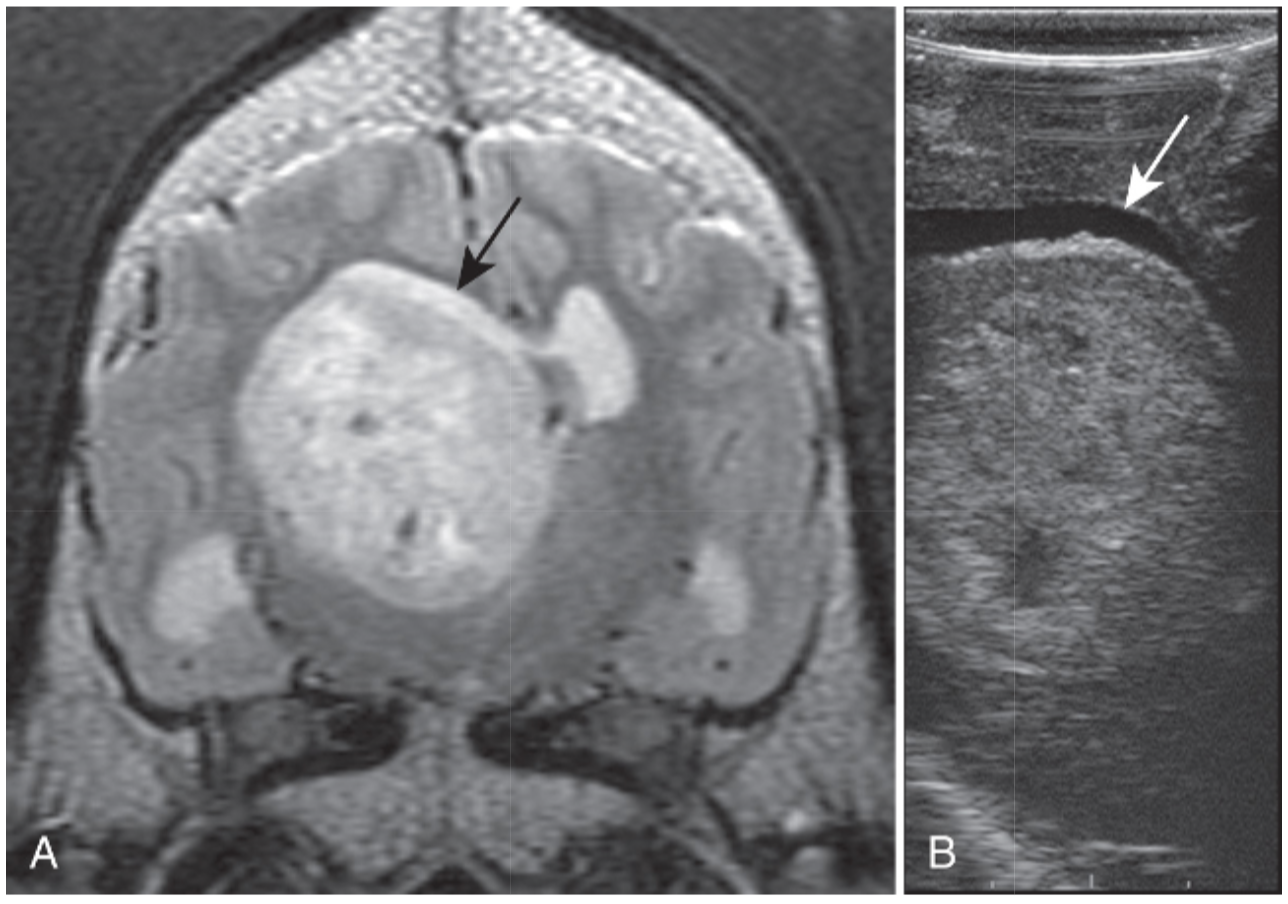

A, On the transverse plane, T2-weighted image, a large hyperintense intraparenchymal, high-grade glioma can be seen displacing the right lateral ventricle that appears crescent shaped and hyperintense (black arrow).

B, Intraoperative ultrasonography clearly defines the location and depth of the mass, and the overlying ventricle is seen as an anechoic rim dorsal to the mass (white arrow).